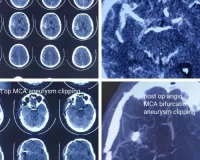

आचार्य एवं ईकाई बी प्रभारी डॉ शरद थानवी ने बताया कि एन्यूरिश्म खून की नलियों की दीवार के कमजोर होने से बने वो गुब्बारे होते है जिनके फटने से मरीज को बहुत तेज सरदर्द होता है। तथा जिसके साथ बेहोश होना, मिर्गी का दौरा आना या हाथ पैर में कमजोरी आना, इत्यादि लक्षण भी आ सकते है। आज से 20 दिन पूर्व 80 वर्षीय महिला को अचेत अवस्था में एमडीएम के न्यूरोसर्जरी विभाग में लाया गया जिसकी सम्पूर्ण जांच मय सीटी स्केन एवं एन्जियोग्राफी करवाने पर पाया गया कि इसके विभाग की एक धमनी एन्टीरियर कम्यूनिकिटिंग ऑर्टरी पर बना गुब्बारा (अकॉम एन्यूरिश्म) फटने से मरीज इस अवस्था में पहुंची है। ऐसी ही बीमारी से ग्रसित 56 वर्षीय पुरूष को तेज सर दर्द की शिकायत के साथ न्यूरोसर्जरी इमरजेन्सी में लाया गया जहां पर सीटी स्केन करवाने पर एन्यूरिश्म के फटे होने की शंका पर सीटी एन्जियोग्राफी करवायी गयी जिसमें मीडल सीरीबल ऑर्टरी (एमसीए) पर बने गुब्बारे का फटना पाया गया।

सहायक आचार्य डॉ हेमन्त बेनीवाल ने बताया कि ऐसे मरीजों की सर्जरी बहुत ही रिस्की होती है जिसमें संबंधित खूनी की नली पर पहुंच कर उस गुब्बारे की नेक पर क्लीप लगाकर खून के बहाव को धमनियों में ही सुरक्षित किया जाता है। ऐसी सर्जरी में अत्यधिक तकनीकी दक्षता की आवश्यकता होती है अन्यथा एन्यूरिश्म में से पुनः रक्त स्राव की संभावना रहती है जिससे मरीज को लकवा आना, आवज चली जाना एवं अन्य विकास होने का खतरा रहता है।

उक्त दोनों मरीजों को माइक्रोसर्जीकल क्लिपिंग द्वारा सफलतापूर्वक ऑपरेशन किया गया। ऑपरेशन के बाद भी अगले 7-15 दिन अत्यधिक क्रिटीकल रहते है अतः मरीजों को आईसीयू में रखकर क्रिटीकल केयर टीम की सहायता से पूर्णतः स्टेबल कर वार्ड में शिफ्ट किया गया। अब दोनों मरीज पूर्णतः स्वस्थ है तथा अगले एक से दो दिन में डिस्चार्ज कर दिया जायेगा।ऑपरेशन टीम में आचार्य एवं ईकाई प्रभारी डॉ शरद थानवी, सहायक आचार्य डॉ हेेमन्त बेनीवाल एवं सीनियर रेजिडेन्ट डॉ सन्दीप कुण्डल एवं डॉ लख्मीचन्द्र शामिल थे। निश्चेतना विभाग की टीम में वरिष्ठ आचार्य डॉ शोभा उज्जवल, आचार्य डॅा गीता सिंगारिया, सहायक आचार्य डॉ. पूजा, सीनियर रेजिडेन्ट डॉ आभास एवं रेजिडेन्ट विनेश, प्रतिमा सम्मिलित थे। सिस्टर रेखा, भारत, मुरली एवं युवराज ने स्टाफ के रूप में ऑपरेशन में सहयोग रहा।